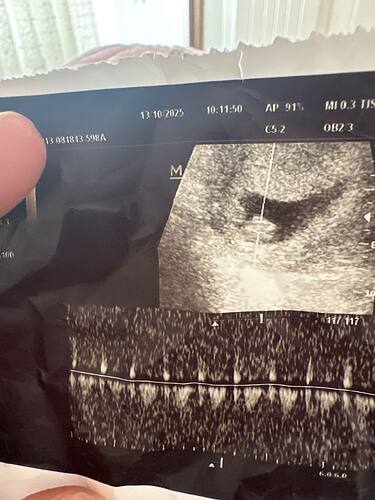

Anladgimdan değil ama erkek hissettim

bence erkek gibi

Erkek gibi

Erkek bebek kesesi gibi balım

Erkek gibii

galiba yuvarlak olanlar kiz yamuk yumuk sekilsizler erkek oluyo sizinki de erkek gibi

Büyük ihtimalle erkek canim

erkek gibi kesesi